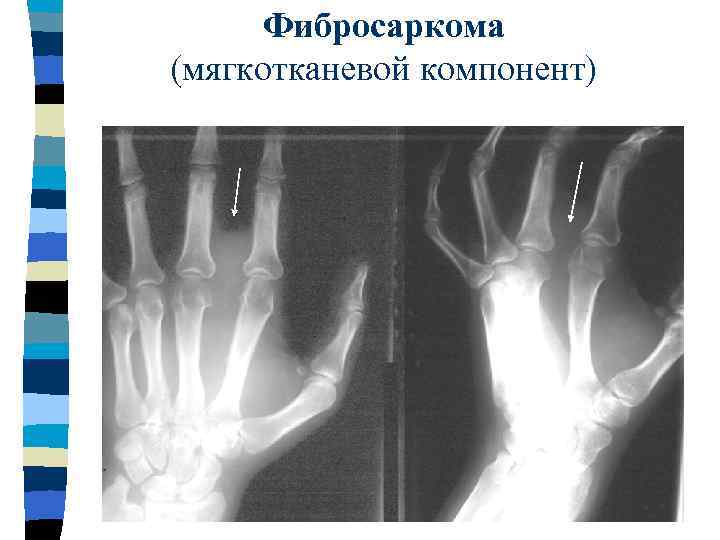

Фибросаркома (мягкотканевой компонент)